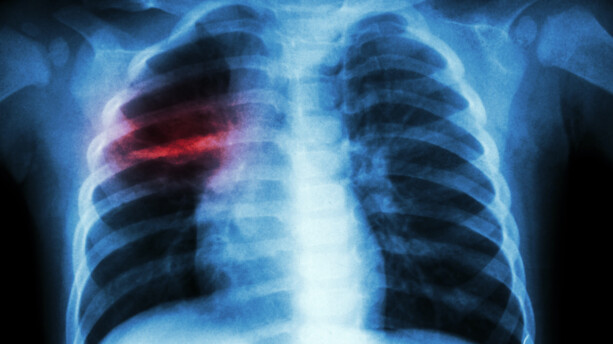

Le 24 mars, En prélude à la Journée mondiale de lutte contre la tuberculose prévue le 24 mars, le coordonnateur du Programme national de lutte contre la tuberculose (PNT), Fodé Danfakha, a fait le point sur la situation de la maladie au Sénégal. Selon ses déclarations, l’année 2024 a enregistré un total de 16 595 cas de tuberculose, toutes formes confondues. Parmi ces cas, une prédominance masculine est à noter, avec 11 181 hommes contre 5 414 femmes touchés par la maladie. Fodé Danfakha a souligné que la tuberculose touche principalement les adultes jeunes. Cette tranche d’âge représente une grande partie de la population active. Ce qui soulève des préoccupations au-delà des enjeux de santé publique. « Cela va avoir un impact socio-économique sur la vie de ces populations. Ce sont des gens qui sont en activité. Cette maladie va impacter leur vie ainsi que leur travail », a-t-il déclaré, soulignant l’importance de la prévention et de la prise en charge rapide de la maladie. La tuberculose demeure un problème majeur de santé publique au Sénégal. Et cette situation met en lumière les défis à relever pour mieux lutter contre la propagation de cette maladie, en particulier chez les jeunes adultes. Selon Dr Danfakha, l’impact de la tuberculose ne se limite pas à la santé des individus, mais se répercute également sur l’économie. Car les malades, souvent en âge de travailler, sont contraints de suspendre leurs activités, ce qui affecte leur productivité et leur bien-être.